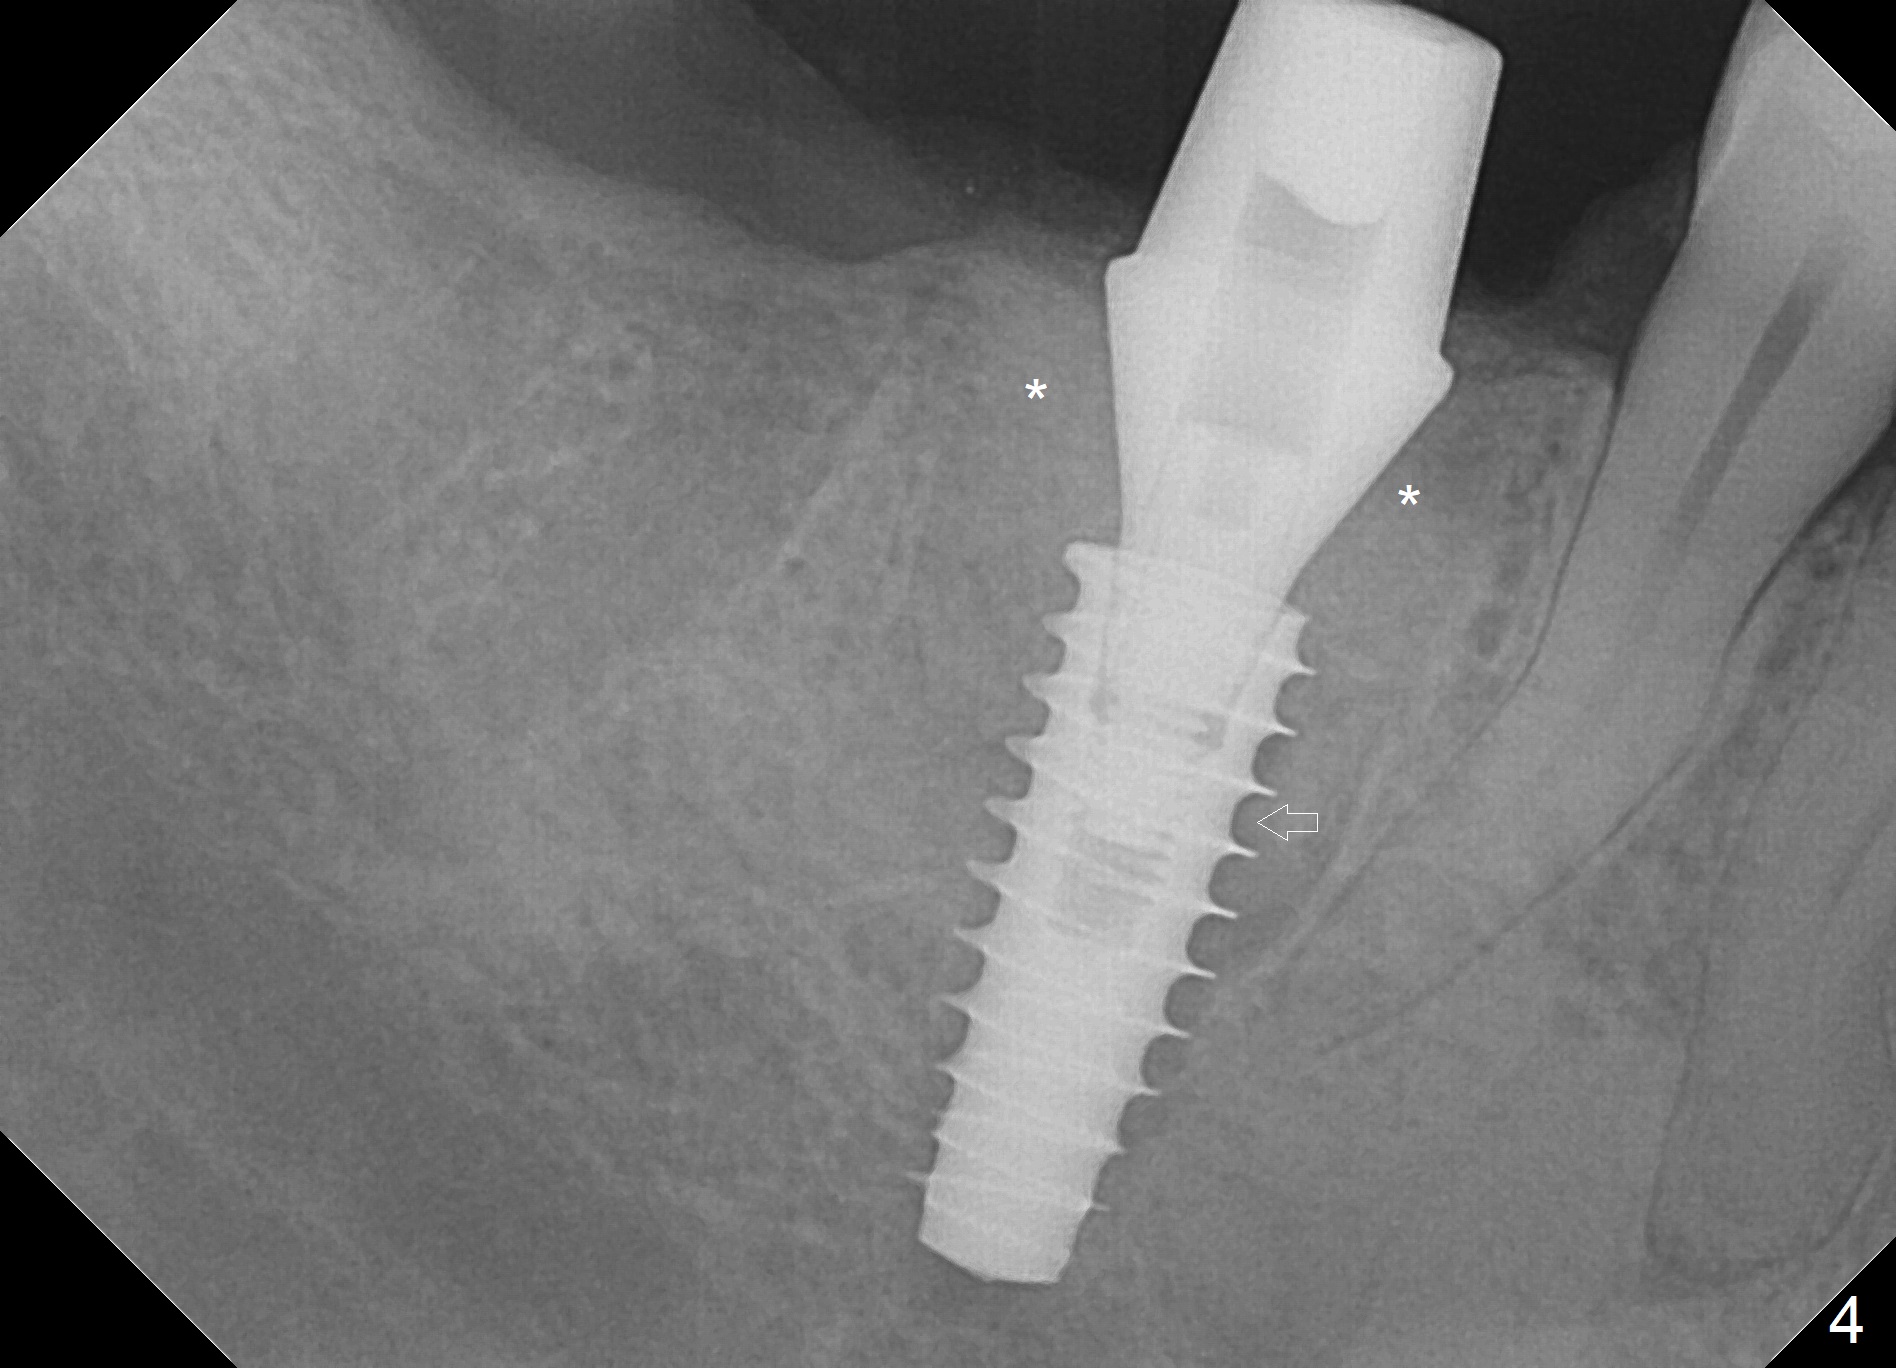

Extraction is difficult due to hard bone and brittle, curved roots of the tooth #30; initial depth in the septum is 14 mm (gingival level, Fig.1). Then the depth increases to 17 mm; with sequential osteotomy using 2.8 mm to 4.8 mm Magic Drills (MD), a 5x9 mm dummy implant is placed incompletely due to hard bone (Fig.2). After use of 5.3 mm MD for ~ 15 mm, the dummy implant is placed to the depth (Fig.3). The definitive IBS implant (5x13 mm) is placed with 50 Ncm; a 6.5x5.7(4) mm abutment is placed with allograft filling the gap (* and arrow).

Bone graft seems to sink down and becomes denser 3 months postop (Fig.6 arrow). The bone continues being denser 5 months postop (Fig.7). There is periapical radiolucency of the tooth #29 (^). RCT is done (Fig.8). The pain persists 2 weeks postop (Fig.9,10). There is no missing canal (Fig.9). The apex is close to the implant (Fig.9 *). Apicoectomy will be performed if needed. It appears that the implant is also placed buccal (Fig.10 <) and/or the implant too large for the site. Therefore there should be a 2-3 mm buccal gap before and after implant placement. Separation and reflection of the buccal flap allows better visibility. The pain persists 1 month post RCT and 6 months post implant placement. RCT retreatment is initiated (Fig.11,12) with placement of Calcium Hydroxide paste after redebridement with 30/.04 rotary file at 23.5 mm (.5 mm longer than the earlier RCT, Fig.13). RCT retreatment finishes with apparent transportation and extrusion in 4 weeks (Fig.14,15), followed by apicoetomy (Fig.16,17) (20 days later)). Discomfort remains 2.5 months postop (Fig.18). Keep watching.